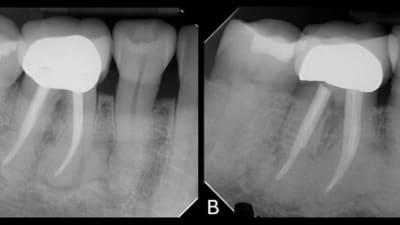

This article presents a clinical case of a comprehensive full-mouth rehabilitation in a 26-yearold female patient with an anterior open bite and accompanying mild chronic generalized periodontitis.